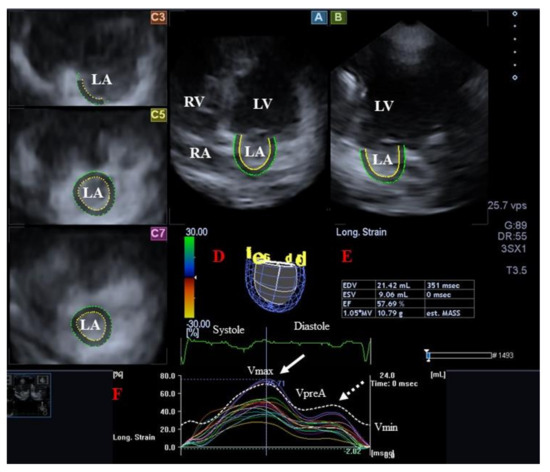

3.2. Left Atrium

3.2.2. In Acromegaly

- Kormányos, Á.; Domsik, P.; Kalapos, A.; Valkusz, Z.; Lengyel, C.; Forster, T.; Nemes, A. Three-dimensional speckle tracking echocardiography-derived left atrial deformation analysis in acromegaly (Results from the MAGYAR-Path Study). Echocardiography 2018, 35, 975–984. [Google Scholar] [CrossRef]